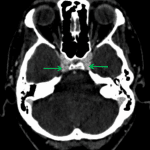

- Nonopacified, engorged left superior ophthalmic vein

- Partial opacification of the left frontal, maxillary, and sphenoid sinuses as well as of multiple left ethmoid air cells with intermixed high density material

- Sinusitis

Findings concerning for sinusitis involving the left frontal, maxillary, and sphenoid sinuses as well as multiple left ethmoid air cells. Intermixed high density material could represent blood products, inspissated secretions, or chronic fungal colonization. Prior left maxillary antrostomy.